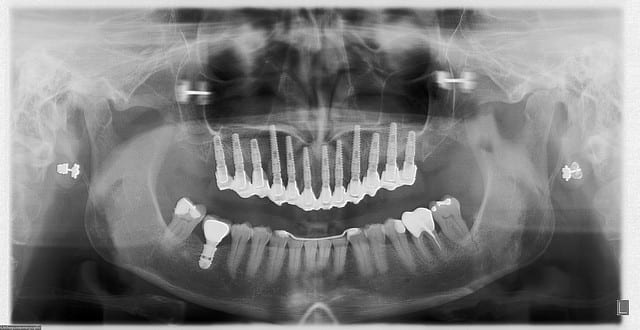

Pano m3k0n5 - Eugenol